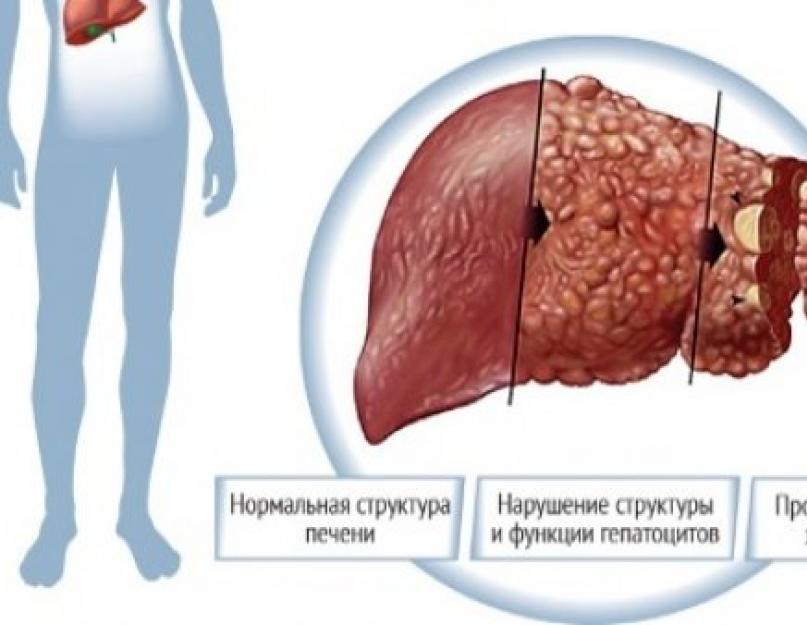

Признаки заболеваний печени: Важные симптомы и рекомендации